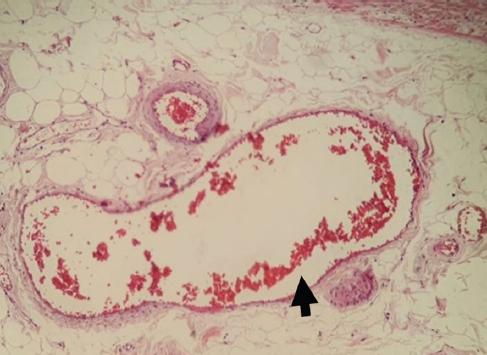

Exploratory laparotomy was performed, finding cone-shaped surgical mesh eroding the parietal peritoneum, with adhesions to the omentum, cecum, and cecal appendix (Fig. 2). A 10x1 cm erythematous, edematous, and hyperemic cecal appendix, with the presence of appendicolith at the tip. Finally, an appendectomy was performed by dismantling the surgical mesh cone and closure of the peritoneum. The mesh was placed using the Lichtenstein technique in its entirety. The patient evolved favorably and was discharged 24 h after surgery. Pathology revealed cecal appendix with reactive lymphatic hyperplasia and passive congestion (Figs. 3-5).

Mesh migration can be divided into primary and secondary migration. Primary migration consists of mesh movement over pathways of least resistance into contiguous anatomical spaces, due to either inadequate mesh fixation or external forces. Secondary mesh migration consists of slow, gradual movements of the mesh across trans-anatomic planes and is secondary to erosion induced by foreign body reaction. This depends on the nature of the mesh biomaterial and the type of fixation. Thus, the mesh may initially be displaced and subsequently erode adjacent tissue4,11.

Since the anatomopathological findings do not coincide with the time of evolution of the clinical condition, it can be assumed that the symptoms were secondary to the erosion of the cecal appendix by the migrated mesh, with subsequent histological changes, thus being a primary type of migration.